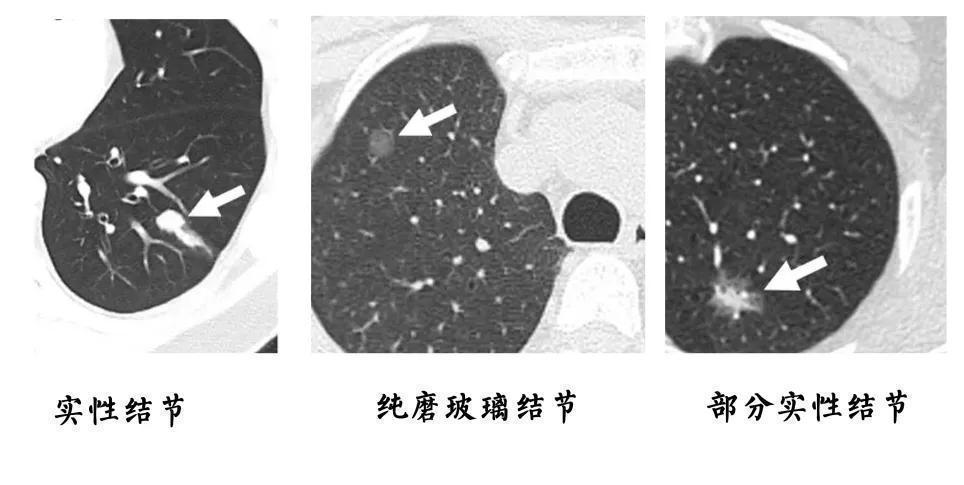

2、根据结节密度判断

肺结节按密度可以分为实性结节、纯磨玻璃结节和部分实性结节。

通常情况下,实性结节和纯磨玻璃结节多为良性结节,部分实性结节是恶性的概率相对较高。